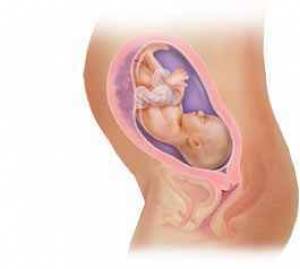

بارداری هفته به هفته و تغییر وضعیت جنین+عکس

بارداری معمولا 280 روز یا 40 هفته بطول می انجامد، که بطور قراردادی از اولین روز آخرین قاعدگی شروع می شود. این دوران را می توان به سه "سه ماهه" بارداری تقسیم کرد که در هر یک وقایع خاصی اتفاق می افتد؛ سه ماهه اول از اولین هفته بارداری تا انتهای هفته 13، سه ماهه دوم از هفته 14 تا پایان هفته 27، و سه ماهه سوم از هفته 28 تا آخر هفته 40 است که عمدتا در این زمان (کمی زودتر یا دیرتر) به زایمان و تولد نوزاد ختم می شود.

هر سه ماهه مشخصات مربوط به خود را دارد؛ در سه ماهه اول ضربان قلب جنین شنیده می شود، در سه ماهه دوم اولین حرکات جنین توسط مادر احساس می شود، و در سه ماهه آخر برخی از مادران انقباضات کاذب زایمانی موسوم به برکستون- هیکز را تجربه می کنند. بعضی از آزمایشات مانند نمونه برداری از پرزهای جفتی در سه ماهه اول و آمنیوسنتز در سه ماهه دوم انجام می شوند. برخی از مسائل مانند دیابت بارداری، در سه ماهه آخر تظاهر می کنند. در این دوران عواطف و احساسات شما نیز مانند بدنتان دستخوش تغییراتی می شود و شرایط زندگی برای خانواده بتدریج آماده پذیرایی از کودک آینده خواهد شد.